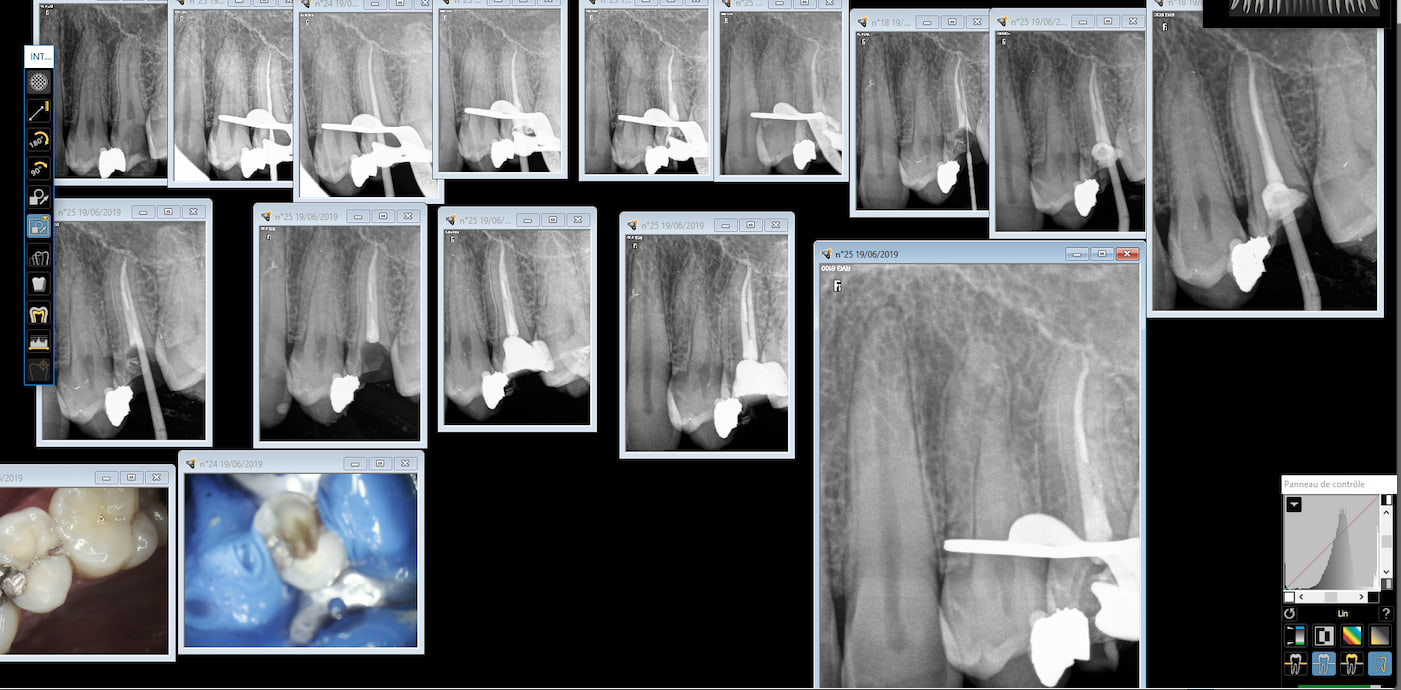

dimanche j'ai passé 6 h pour faire 2 plans conformes à partir d'un shéma sur un papier chiffoné

mes classeurs comportent entre 30 et 60 pages

20/06/2019 à 15h30

il y a aussi une floppée de xxx qui profite qu'on ne leur demande rien pour en faire encore moins

exemple : tiens il n'y a rien qui m'empêche de faire une feuille pour un bridge sur implant alors "allons-y"

et après on s'est retrouvé 40 000 avec une case à cocher en plus

dans le temps on déclarait son générateur à l'ouverture et on le jetait à la benne à la retraite

entre les 2 ===> RIEN